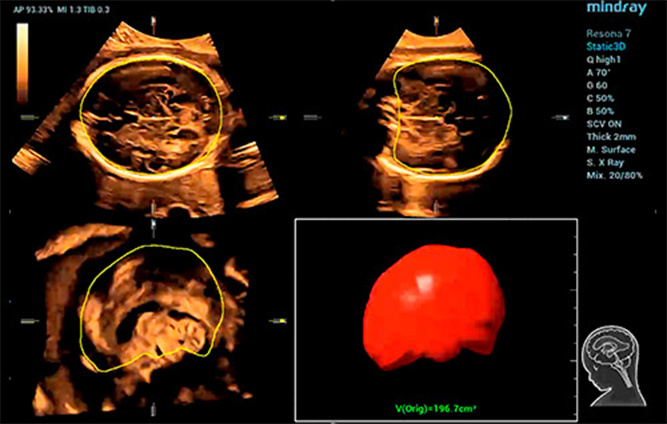

Smart ICV: CƔlculo automƔtico del volumen intracraneal

Para reducir la dependencia del usuario y mejorar la eficiencia del diagnĆ³stico, Mindray desarrollĆ³ una innovadora interacciĆ³n 3D/4D basada en situaciones clĆnicas para contextos tĆpicos de exĆ”menes de ecografĆa 3D (como los del cerebro, el rostro, la columna vertebral y los huesos largos del feto). Esta soluciĆ³n permite la identificaciĆ³n automĆ”tica de escenas, la optimizaciĆ³n automĆ”tica de las imĆ”genes, la captaciĆ³n automĆ”tica de planos y la cuantificaciĆ³n automĆ”tica con un solo clic. Realmente hace posible un flujo de trabajo automĆ”tico durante todo el procedimiento, lo que otorga una fuerte confianza en el diagnĆ³stico para una mejor atenciĆ³n del paciente.